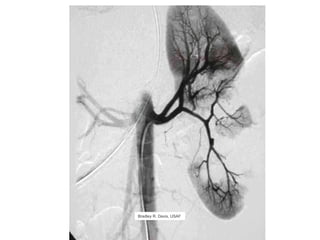

The kidneys can be injured by blunt or penetrating trauma, requiring timely medical evaluation. The kidneys are normally protected by back muscles but can be damaged by severe impacts or objects piercing the skin. Blunt trauma may cause bruising while penetrating injuries like gunshots can enter elsewhere and travel to the kidneys. Most kidney injuries are minor but evaluation with imaging tests like ultrasound or CT scans helps classify the injury and guide management, which may include rest, antibiotics, surgery, or nephrectomy in more severe cases.